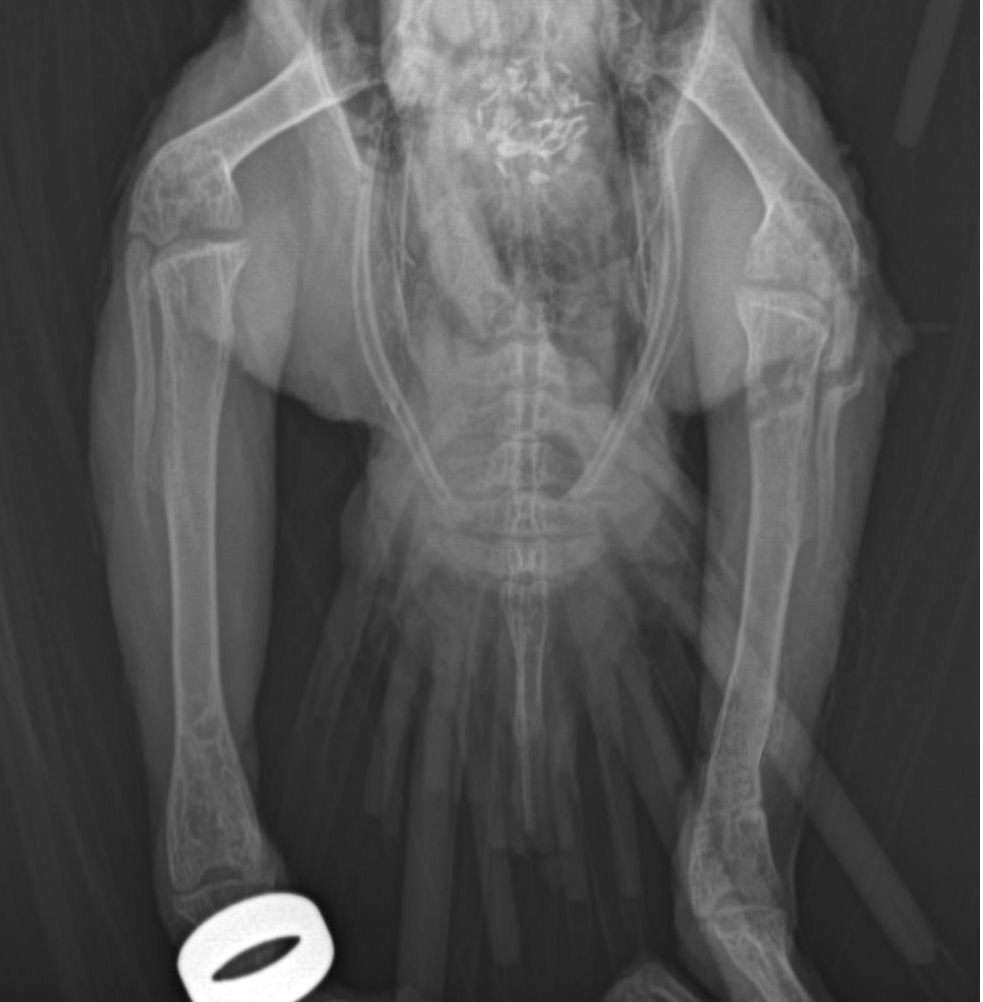

正位x光片

侧位x光片 该鹦鹉左后肢胫骨中后端横向骨折